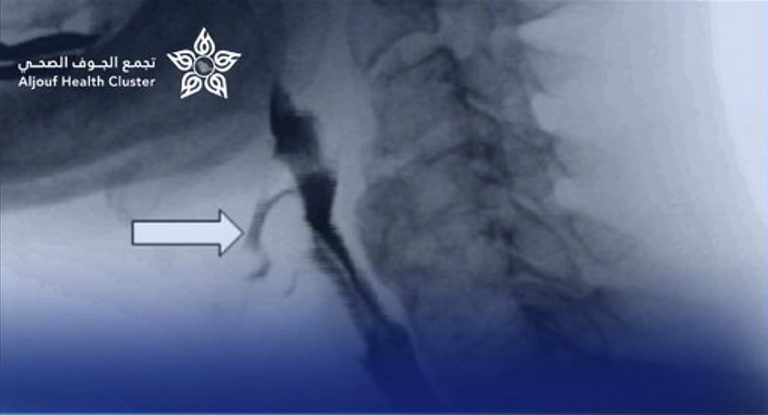

نجاح توسعة مريء لطفل بالمنظار دون تدخل جراحي في «تخصصي الجوف»

نجح فريق طبي متخصص من قسم الجهاز الهضمي للأطفال وقسم التخدير بمستشفى الملك عبد العزيز التخصصي بالجوف، بالتعاون مع مستشفى النساء والولادة والأطفال، في إجراء عملية توسيع للمريء بالمنظار لطفل يبلغ من العمر 11 عامًا، دون الحاجة إلى أي تدخل جراحي.